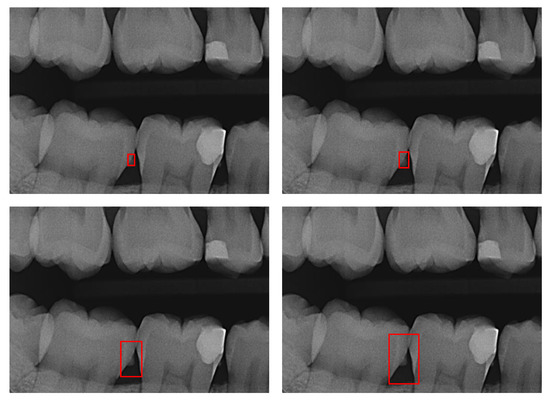

Figure 4 shows an evaluation of a detection using SHAP. Red values represent a positive contribution of the super pixel to the detection and blue values a contribution against it. Even with an area enlargement by a factor of 100, visible calculus still played an important role for the detection.

Figure 4. XAI evaluation. First row: Model prediction (green rectangle) trained on annotation with α = 1, α = 10, α = 100 (from left to right). Second row: SHapley Additive exPlanations (SHAP) heatmap where red values represent a positive contribution of the super pixel to the detection and blue values a negative contribution.

Evaluating the models with XAI methods as shown in Figure 4 gives us insights into possible causes: calculus remained most relevant for models prediction even when trained using large BBs; the super-pixels used to decide where calculus is present were near identical regardless of the BB size. Additional pixels included in the enlarged BB (α = 100) played a subordinate role for the prediction, likely as the standardization of the image (bitewings are similar to each other, which is different in comparison with natural scene images) allowed the model to learn the background and consequently ignore it successfully even if BBs were too large. The illustration of the predictions further show that the object (calculus) remained center of the predicted BBs. This reinforces the assumption that the model has learned the annotation error (consistently too large BBs). This phenomenon might be further explained by the learning process of neural networks: the model is optimized to predict BBs as close to the ground truth as possible. To increase the performance the objective thus becomes: (1) identification of the object of interest (calculus); (2) fit BB with dimensions to maximize area overlap with ground truth (e.g., consistently too large).